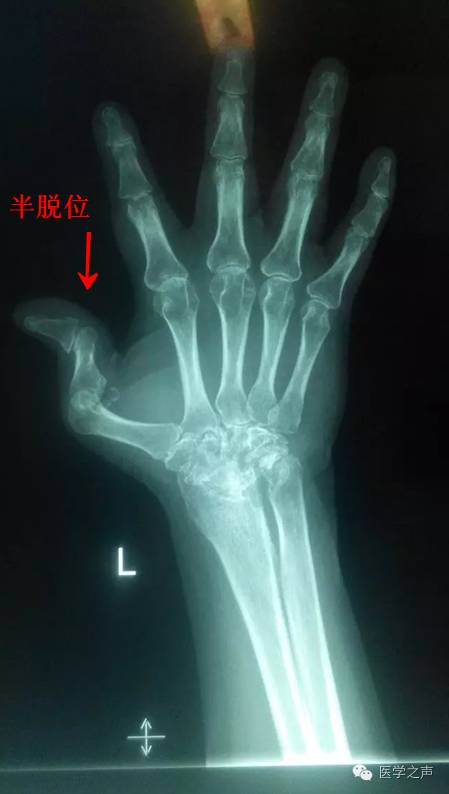

双手指间关节周围软组织稍肿胀,关节面模糊,关节间隙变窄,关节邻近骨质疏松,其间可见斑点状及小囊状骨质密度减低区,左手第1掌指关节及右手第5指关节呈半脱位,各腕骨骨质疏松,边缘不清,见斑点状及小囊状骨质密度减低区。

1.双手类风湿性关节炎。

2.左手第1掌指关节及右手第5指关节呈半脱位。